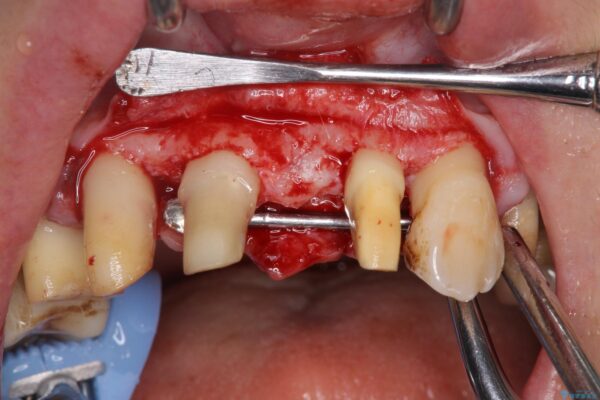

治療中

歯の総合的なマネージメントを行う包括的歯科治療の実践[ 歯周病・矯正・セラミック補綴 ] 治療中画像 歯の総合的なマネージメントを行う包括的歯科治療の実践[ 歯周病・矯正・セラミック補綴 ] 治療中画像 歯の総合的なマネージメントを行う包括的歯科治療の実践[ 歯周病・矯正・セラミック補綴 ] 治療中画像 歯の総合的なマネージメントを行う包括的歯科治療の実践[ 歯周病・矯正・セラミック補綴 ] 治療中画像 歯の総合的なマネージメントを行う包括的歯科治療の実践[ 歯周病・矯正・セラミック補綴 ] 治療中画像 歯の総合的なマネージメントを行う包括的歯科治療の実践[ 歯周病・矯正・セラミック補綴 ] 治療中画像 歯の総合的なマネージメントを行う包括的歯科治療の実践[ 歯周病・矯正・セラミック補綴 ] 治療中画像 歯の総合的なマネージメントを行う包括的歯科治療の実践[ 歯周病・矯正・セラミック補綴 ] 治療中画像 歯の総合的なマネージメントを行う包括的歯科治療の実践[ 歯周病・矯正・セラミック補綴 ] 治療中画像 歯の総合的なマネージメントを行う包括的歯科治療の実践[ 歯周病・矯正・セラミック補綴 ] 治療中画像 歯の総合的なマネージメントを行う包括的歯科治療の実践[ 歯周病・矯正・セラミック補綴 ] 治療中画像

まず、保存の難しい歯を抜去したのち矯正治療を行い歯並びの改善、歯周ポケットを除去したことで安定した歯周環境、咬合関係を作り出すことができました。